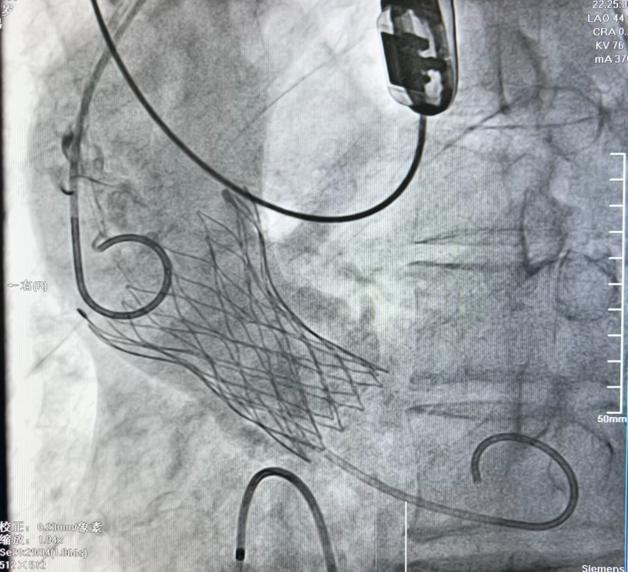

患者之二为71岁男性,近10天来间断胸闷不适,既往有血压升高史,来院就诊胸部CT提示心影增大,心电图显示窦性心律、ST改变,心脏超声提示主动脉瓣二叶瓣畸形,伴重度钙化及狭窄,左室壁增厚,左心收缩功能减退,跨瓣压差107mmHg。入院诊断为主动脉瓣重度狭窄、慢性心功能不全急性加重、心功能II--III级(NYHA分级)。在顺利植入TaurusElite AV26瓣膜术后,超声结果显示跨瓣压差降至8mmHg,手术取得圆满成功。

病例1:重度主动脉瓣关闭不全瓣膜植入 病例2:重度主动脉瓣狭窄瓣膜植入